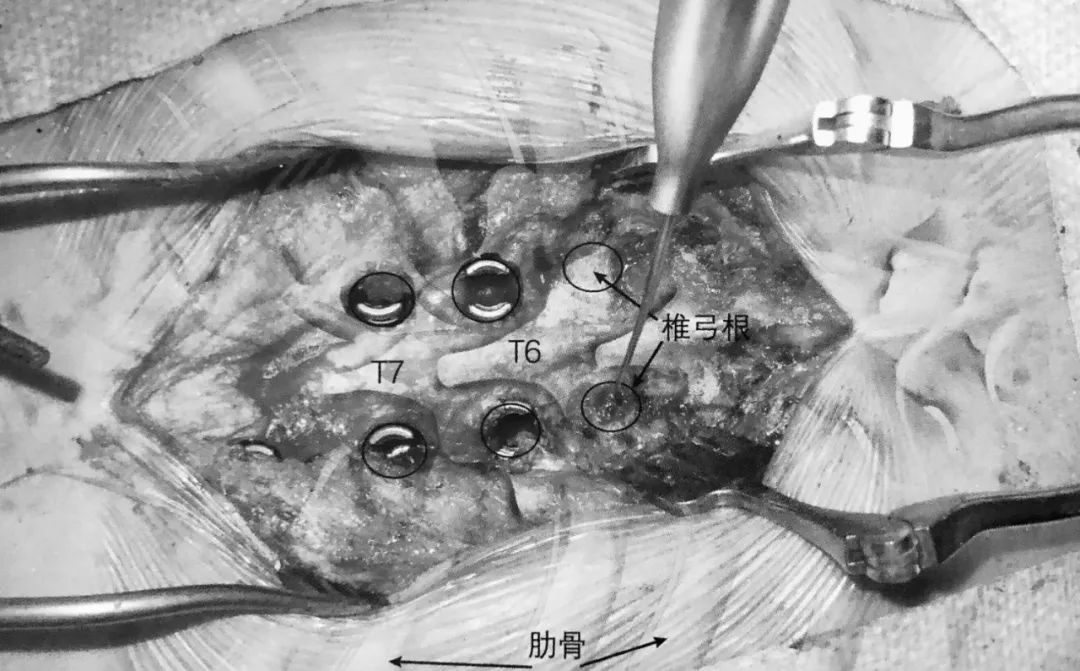

1. 术前准备要点:

2. 术中使用双平面透视机。

3. 球囊套管的开口点应位于椎弓根的 10 点或 2 点位置即上外侧角,取决于左右。将置入通道设计于该处可保证其离神经根最远。如前后位片所示插入通道,侧位片上套管通过椎体后缘线之前不能越过椎弓根内壁。

4. 通道开口点位于关节突关节外侧,这样可以避免损伤关节囊。

5. 术中透视证实球囊位于椎体前部,这可避免骨折块向后突入椎管。

6. 球囊充气为骨水泥注入建立潜在空间。

7. 透视下向椎体内注入骨水泥,在正侧位片上仔细观察以确保椎体边缘不被侵犯。如果发现骨水泥溢出,则停止注入。应避免将骨水泥注入椎体后部。

8. 理想情况下,正位片上骨水泥充填应该通过中线。

9. 潜在风险:

严重骨质疏松导致透视效果差

骨水泥栓塞

骨水泥向椎间孔或椎管溢出

套管置入不当引起椎弓根骨折

骨水泥充填不足

8. 潜在风险:

椎弓根钉侵犯内侧和下壁可能损伤神经根和脊髓

螺钉太长侵犯前方骨皮质可能导致血管或内脏损伤

椎弓根螺钉置钉位置不当可能引起螺钉拔出或固定失败